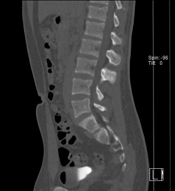

CT scan of a spineBefore choosing an imaging center, parents should ask the following questions: